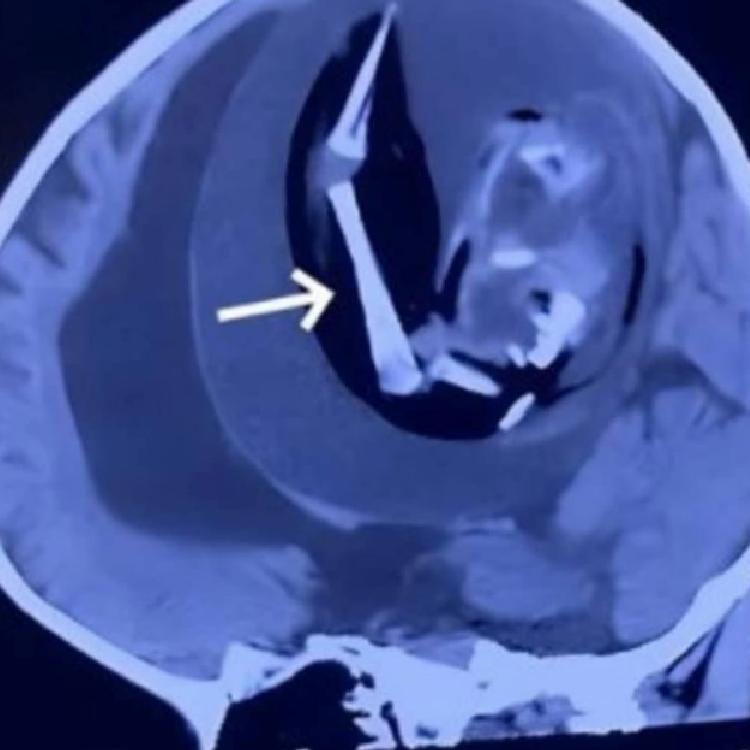

Aile, bebeklerinin motor becerilerinde yaşadığı sorunlar ve kafatasındaki aşırı büyüme nedeniyle hastaneye başvurdu. Yapılan MR görüntülemeleri, tıp camiasını şaşkına çevirdi. Bebeklerinin kafasında kemiksi bir yapı tespit edildi ve detaylı incelemeler sonucunda, bu yapının aslında gelişimini tamamlayamamış bir fetüs olduğu belirlendi.

Bebeğin durumu üzerine hemen ameliyat kararı alındı. Doktorların tüm çabalarına rağmen, 1 yaşındaki bebek kurtarılamadı. Ameliyat sırasında bebeğin kafasından; omurgası, gözleri, ağzı ve kolları gibi birçok organı gelişmiş bir fetüs çıkarıldı.